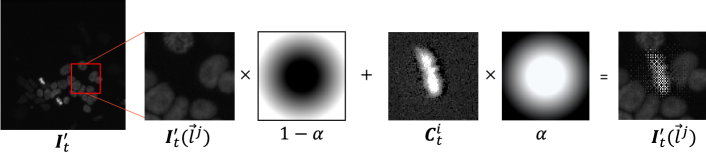

Figure 4: Illustration of alpha-blending pasting.

Mitosis label utilization with alpha-blending pasting: Next, we paste mitosis events to the flipped pair by using copy-and-paste techniques in order to utilize the positive labels effectively. Copy and paste augmentation has been used for supervised augmentation of instance segmentation [4]. Unlike instance segmentation with object masks, we only have locations (t, x, y). A simple solution is to crop images around the mitosis position and copy and paste them to the target image, like in CutMix [23]. However, the cropped image naturally contains surrounding objects, and the generated image appears unnatural. Unnatural images cause the detection network to make biased predictions and reduce generalization performance. To avoid this problem, we propose alpha-blending pasting with a Gaussian blending mask. We blend two images by leaving the pixel value in the center and blurring the vicinity of the edge of the image.

First, we crop the image around the positive annotations and obtain a set of cropped pair 𝒞={(𝑪t1i,𝑪ti)}i=0N𝒞subscriptsuperscriptsuperscriptsubscript𝑪𝑡1𝑖superscriptsubscript𝑪𝑡𝑖𝑁𝑖0\mathcal{C}=\{(\bm{C}_{t-1}^{i},\bm{C}_{t}^{i})\}^{N}_{i=0} and initialize (𝑰t1,𝑰t)=(𝑰t,𝑰t1)subscriptsuperscript𝑰𝑡1subscriptsuperscript𝑰𝑡subscript𝑰𝑡subscript𝑰𝑡1(\bm{I}^{\prime}_{t-1},\bm{I}^{\prime}_{t})=(\bm{I}_{t},\bm{I}_{t-1}) and 𝒫t={}superscriptsubscript𝒫𝑡\mathcal{P}_{t}^{\prime}=\{\}. Here, N𝑁N is the total number of partial annotations, while 𝑪t1isuperscriptsubscript𝑪𝑡1𝑖\bm{C}_{t-1}^{i} and 𝑪tisuperscriptsubscript𝑪𝑡𝑖\bm{C}_{t}^{i} are images before and after the mitosis of the i𝑖i-th annotation (Fig. 3). Define 𝑰t(lj)superscriptsubscript𝑰𝑡superscript𝑙𝑗\bm{I}_{t}^{\prime}(\vec{l}^{j}), 𝑰t1(lj)superscriptsubscript𝑰𝑡1superscript𝑙𝑗\bm{I}_{t-1}^{\prime}(\vec{l}^{j}) as a cropped pair image at the j𝑗j-th random spatial location ljsuperscript𝑙𝑗\vec{l}^{j}. We crop each image centered at ljsuperscript𝑙𝑗\vec{l}^{j} to a size that is the same as that of 𝑪tisuperscriptsubscript𝑪𝑡𝑖\bm{C}_{t}^{i}. We update the randomly selected patch 𝑰t(lj)superscriptsubscript𝑰𝑡superscript𝑙𝑗\bm{I}_{t}^{\prime}(\vec{l}^{j}), 𝑰t1(lj)superscriptsubscript𝑰𝑡1superscript𝑙𝑗\bm{I}_{t-1}^{\prime}(\vec{l}^{j}) by blending a randomly selected cropped pair (𝑪t1i,𝑪ti)superscriptsubscript𝑪𝑡1𝑖superscriptsubscript𝑪𝑡𝑖(\bm{C}_{t-1}^{i},\bm{C}_{t}^{i}) with the following formula: 𝑰t(lj)=(1α)𝑰t(lj)+α𝑪tisuperscriptsubscript𝑰𝑡superscript𝑙𝑗direct-product1𝛼superscriptsubscript𝑰𝑡superscript𝑙𝑗direct-product𝛼superscriptsubscript𝑪𝑡𝑖\bm{I}_{t}^{\prime}(\vec{l}^{j})=(1-\alpha)\odot\bm{I}_{t}^{\prime}(\vec{l}^{j})+\alpha\odot\bm{C}_{t}^{i}, where α𝛼\alpha is a Gaussian blending mask (Fig. 4). We generate the blending mask by blurring a binary mask around the annotation with a Gaussian filter. We use a random sigma value for the Gaussian filter. Then, we add the paste location ljsuperscript𝑙𝑗\vec{l}^{j} to the set 𝒫tsuperscriptsubscript𝒫𝑡\mathcal{P}_{t}^{\prime}. We repeat this process random k𝑘k times.